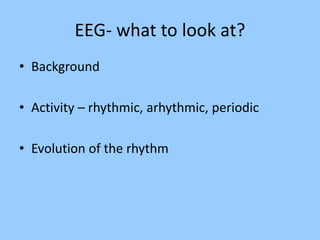

3. International standards for EEG electrode placement and recording parameters are reviewed. Characteristics of different EEG waves, amplitudes, and patterns are described.